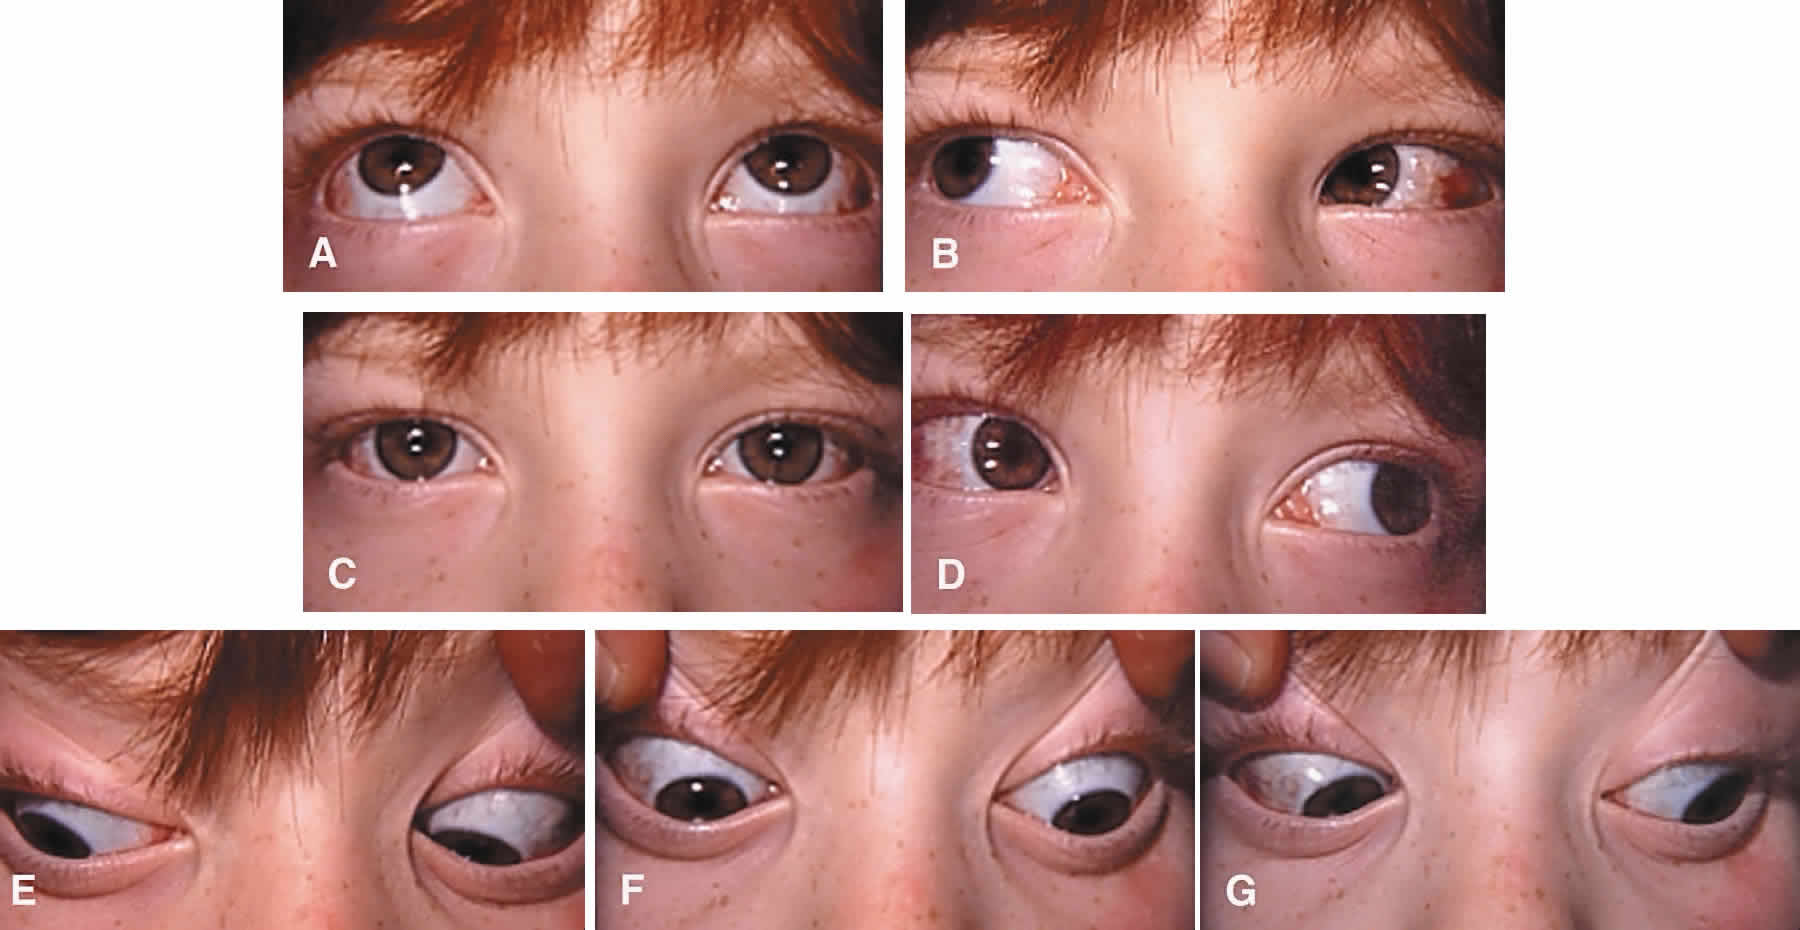

Iatrogenic Brown's syndrome is an unavoidable complication of superior oblique muscle strengthening and occurs in almost 100% of patients undergoing superior oblique tendon tuck. It is virtually identical in clinical appearance to congenital Brown's syndrome, which is discussed later in this chapter (Fig. 10). In the absence of excessive tendon shortening, the limitation of elevation in adduction almost always improves with time and reoperation for this entity is rarely required. Tendon tucking medially (rather than temporally) to the superior rectus muscle is more hazardous because of proximity to the trochlea. Patients with persisting overcorrection in primary gaze position and at least moderate Brown's syndrome (no elevation above the horizontal meridian in adduction) are usually symptomatic and should have their tucks removed. However, adhesions between the superior rectus muscle, superior oblique tendon, and the globe are likely to be present and must be freed to normalize ductions. In general, tuck take down should be performed without simultaneous surgery on other cyclovertical muscles.